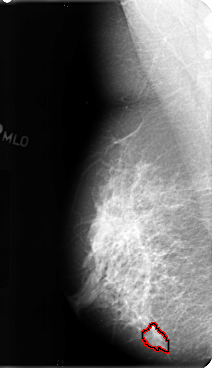

B_3128_1.RIGHT_CC

RIGHT_CC LINES 4792 PIXELS_PER_LINE 2664 BITS_PER_PIXEL 12 RESOLUTION 50 OVERLAY

FILE: B_3128_1.RIGHT_CC.OVERLAY

TOTAL_ABNORMALITIES 1

ABNORMALITY 1

LESION_TYPE MASS SHAPE IRREGULAR MARGINS ILL_DEFINED-SPICULATED

ASSESSMENT 4

SUBTLETY 2

PATHOLOGY BENIGN

TOTAL_OUTLINES 1

BOUNDARY